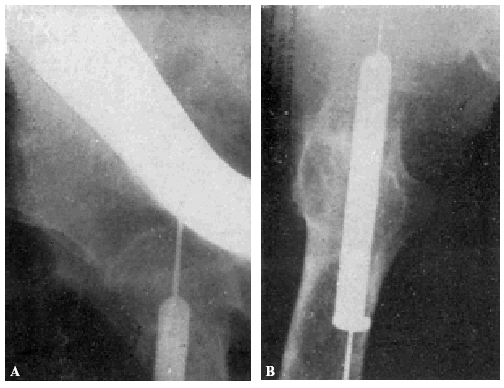

En un caso nuestro, en que el clavo era intolerante y provocaba una supuración (obs. núm. 18), la extracción de éste con raquianestesia, a los cinco meses del enclavijamiento provocó la muerte de la enferma a la media hora de la intervención, probablemente por embolia (fig. 17, A y B). Considerando en este caso la muerte como provocada por el enclavijamiento, la mortalidad de nuestra estadística asciende a 2,8 por 100 (Böhler-Jeschke, 3,8 por 100; García Díaz, 4 por 100).

Teniendo en cuenta el mal estado general de la enferma se procede a la tracción continua, con ocho kilos de peso, mediante el procedimiento de Kirschner. A los ocho días ha mejorado extraordinariamente el estado general de la enferma, procediendo entonces a la osteosíntesis. Hay que advertir que la radiografía anteroposterior ha sido practicada antes de la completa penetración del clavo (fig. 2., A y B).

Figura 2. A: obs. núm. 8. Radiografía practicada antes de la completa penetración del clavo. Este está colocado en una posición demasiado craneal. B: Obs. núm. 8. El clavo fue colocado siguiendo la dirección del Kirschner superior. C: obs. núm. 8. El clavo se ha salido de la cabeza por su parte superior y su punta está situada a nivel de la parte superior de la caja cotiloide.

La radiografía (fig. 2., C) demuestra que el trocáncer ha ido ascendiendo, cortando el clavo el hemisferio superior de la cabeza hasta que, por haber chocado con la ceja cotiloidea, la ascensión del trocánter se ha detenido; pero entonces la pelvis ha basculado, ascendiendo la cresta ilíaca de este lado.

Actualmente nuestra mayor experiencia nos permite afirmar que el clavo, en este caso, había sido colocado demasiado cranealmente, y que, con toda probabilidad, una mejor exploración del estado general de la enferma nos hubiera indicado la inoperancia de la intervención.